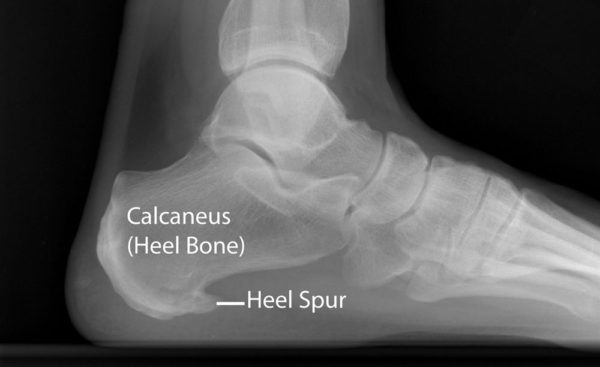

What are heel spurs and how are they related to heel pain?

In many cases, plantar heel pain is associated with a heel spur. You can’t see them but they will show up on an x-ray and may cause a tender patch at the heel on the sole of the foot. A heel spur is where the plantar foot muscle tears and bleeds where it attaches at the heel and, over time, these injuries calcify and form a painful outgrowth off bone.

Your Podiatrist will take a detailed history, analyse your commonly worn footwear and conduct a physical assessment of your foot and lower limb function. They will feel around the site of pain to get an understanding on the integrity of the structures in the area. An X-ray and ultrasound is usually recommended.